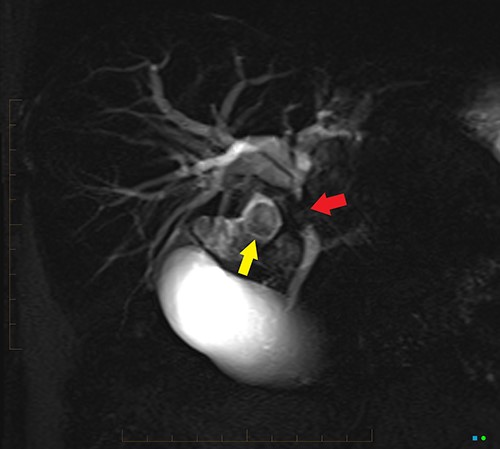

An ultrasound of the abdomen revealed a large gallstone in the gallbladder neck measuring 36 mm with mild biliary dilatation (Fig. 1). Magnetic resonance cholangiopancreatography (MRCP) revealed an irregular long stricture of the extrahepatic bile duct beginning distal to the primary biliary confluence, involving the common hepatic duct for a distance of 20 mm (Fig. 2). A multiphase liver magnetic resonance imaging was performed which confirmed a malignant appearing stricture of the common hepatic duct and showed an ill-defined soft tissue lesion in the porta hepatis between the gallbladder neck and the common hepatic duct (Fig. 3). Her Ca 19.9 was 160 kU/L (ref range < 35 kU/L).

2D projectional MRCP reveals abrupt segmental stricture (red arrow) of the common hepatic duct with marked intrahepatic biliary dilation. Gall bladder is distended and there is a calculus (yellow arrow) in the gall bladder neck.

MIP reconstruction of 3D MRCP reveals abrupt segmental stricture of the common hepatic duct with marked intrahepatic biliary dilation. Trifurcation of the biliary confluence into the left hepatic duct, aberrant segment 6 duct and the right hepatic duct. The right hepatic duct is formed by the union of right anterior (segment 5,8) duct and segment 7 duct while the segment 6 duct is joining separately at the confluence. The approximate plane of surgical resection is indicated.

The patient underwent an open pancreaticoduodenectomy and cholecystectomy. Surgical resection was extended proximally to include the biliary confluence and biliary transection was performed to reveal four separate bile duct openings consisting of the right anterior and posterior sectoral ducts, a separate segment 6 duct and the left hepatic duct (Fig. 4).